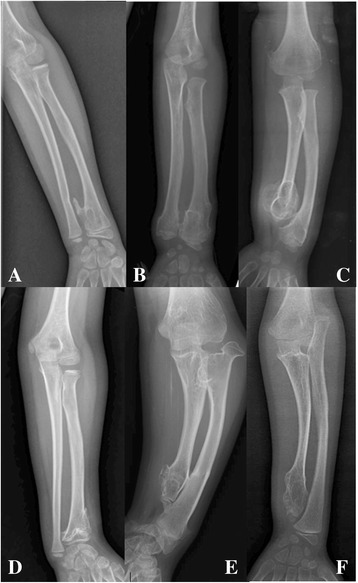

Forearm deformities and lower-extremity malalignments were the most common and obvious deformities of appearance. When assessing forearm deformities, we noted that forearms with exostoses at both the distal radius and ulna without obvious deformities or proportional shortening of the radius and ulna cannot be classified according to the Masada classification [9]. Therefore, we defined these deformities as type 0 and established the following ordinal grading system for forearm deformities: Grade 1, no exostoses of the distal forearm; Grade 2, exostoses of the distal radius or ulna without shortening of either bone or proportionate shortening; Grade 3, exostoses of the distal ulna or radius resulting in a relatively shortened ulna and a bowing radius or a relatively shortened radius, including Masada type I and type III; and Grade 4, exostoses of the distal ulna, a relatively shortened ulna, and a dislocated radial head, described as Masada type IIa and type IIb (Fig. 1). On standing plain films, the normal coronal plane alignment of the lower extremities is determined by the mechanical axis passing from the centre of the femoral head to the ankle; mechanical axis deviation (knee varus or valgus) occurs if the axis is not past the centre of the knee joint.

Fig. 1.

a-b Grade 2, exostoses of the distal radius or ulna without obvious shortening of either bone or proportionate shortening; c Grade 3, Masada type I, exostoses of the distal ulna or radius resulting in a relatively shortened ulna and a bowing radius; d Grade 3, Masada type III, exostoses affected distal radius and resulted in a relatively shortened radius; e Grade 4, exostoses at the distal ulna and the proximal metaphysis of the radius, a relatively shortened ulna and dislocated radial head described as Masada type IIa; f Grade 4, Masada type IIb, the radial head is dislocated without a proximal radial exostosis